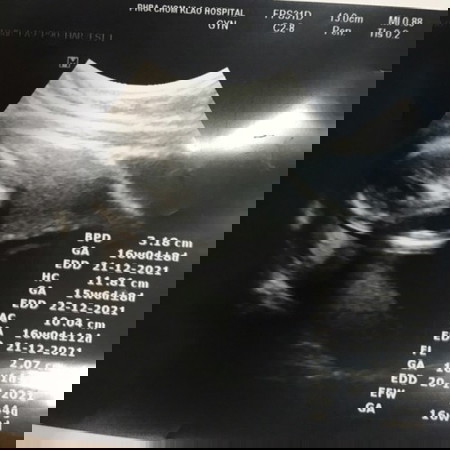

ครรภ์ 16 w. ดูยังไงค่ะภาพซาวน์ ใครดูเป็นบอกบุญหนูหน่อยจ้า

ครรภ์ 16 w. ดูยังไงค่ะภาพซาวน์. อธิบายหนูน่อยตรงไหนตัว หัวค่ะ ดูไม่เป็นจ้า. ท้องแรก แบบนี้ปกติมั้ยค่ะ

ข้างซ้ายน่าจะเป็นหัวรึป่าวคะหลังอยู่ด้านล่างมองยากมากค่ะ ของบ้านนี้เป็นแบบนี้ค่ะซาวด์ตอน15w